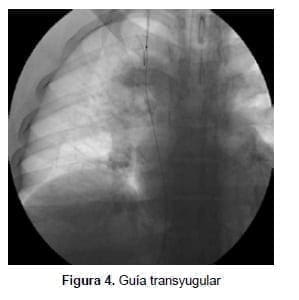

Se procedió a practicar la cavografía de control con oclusión fija en la vena cava inferior perihepática con una guía de 0,035 pulgadas hidrofílica más un catéter multipropósito (Cordis ™ – Johnson & Johnson), logrando pasar a la aurícula derecha. De igual manera se recuperó esta guía por la vía yugular interna con un snare o recuperador de cuerpo extraño (Merit Medical Corp.) y se extrajo por el cuello para poder tener una guía transyugular (figura 4).